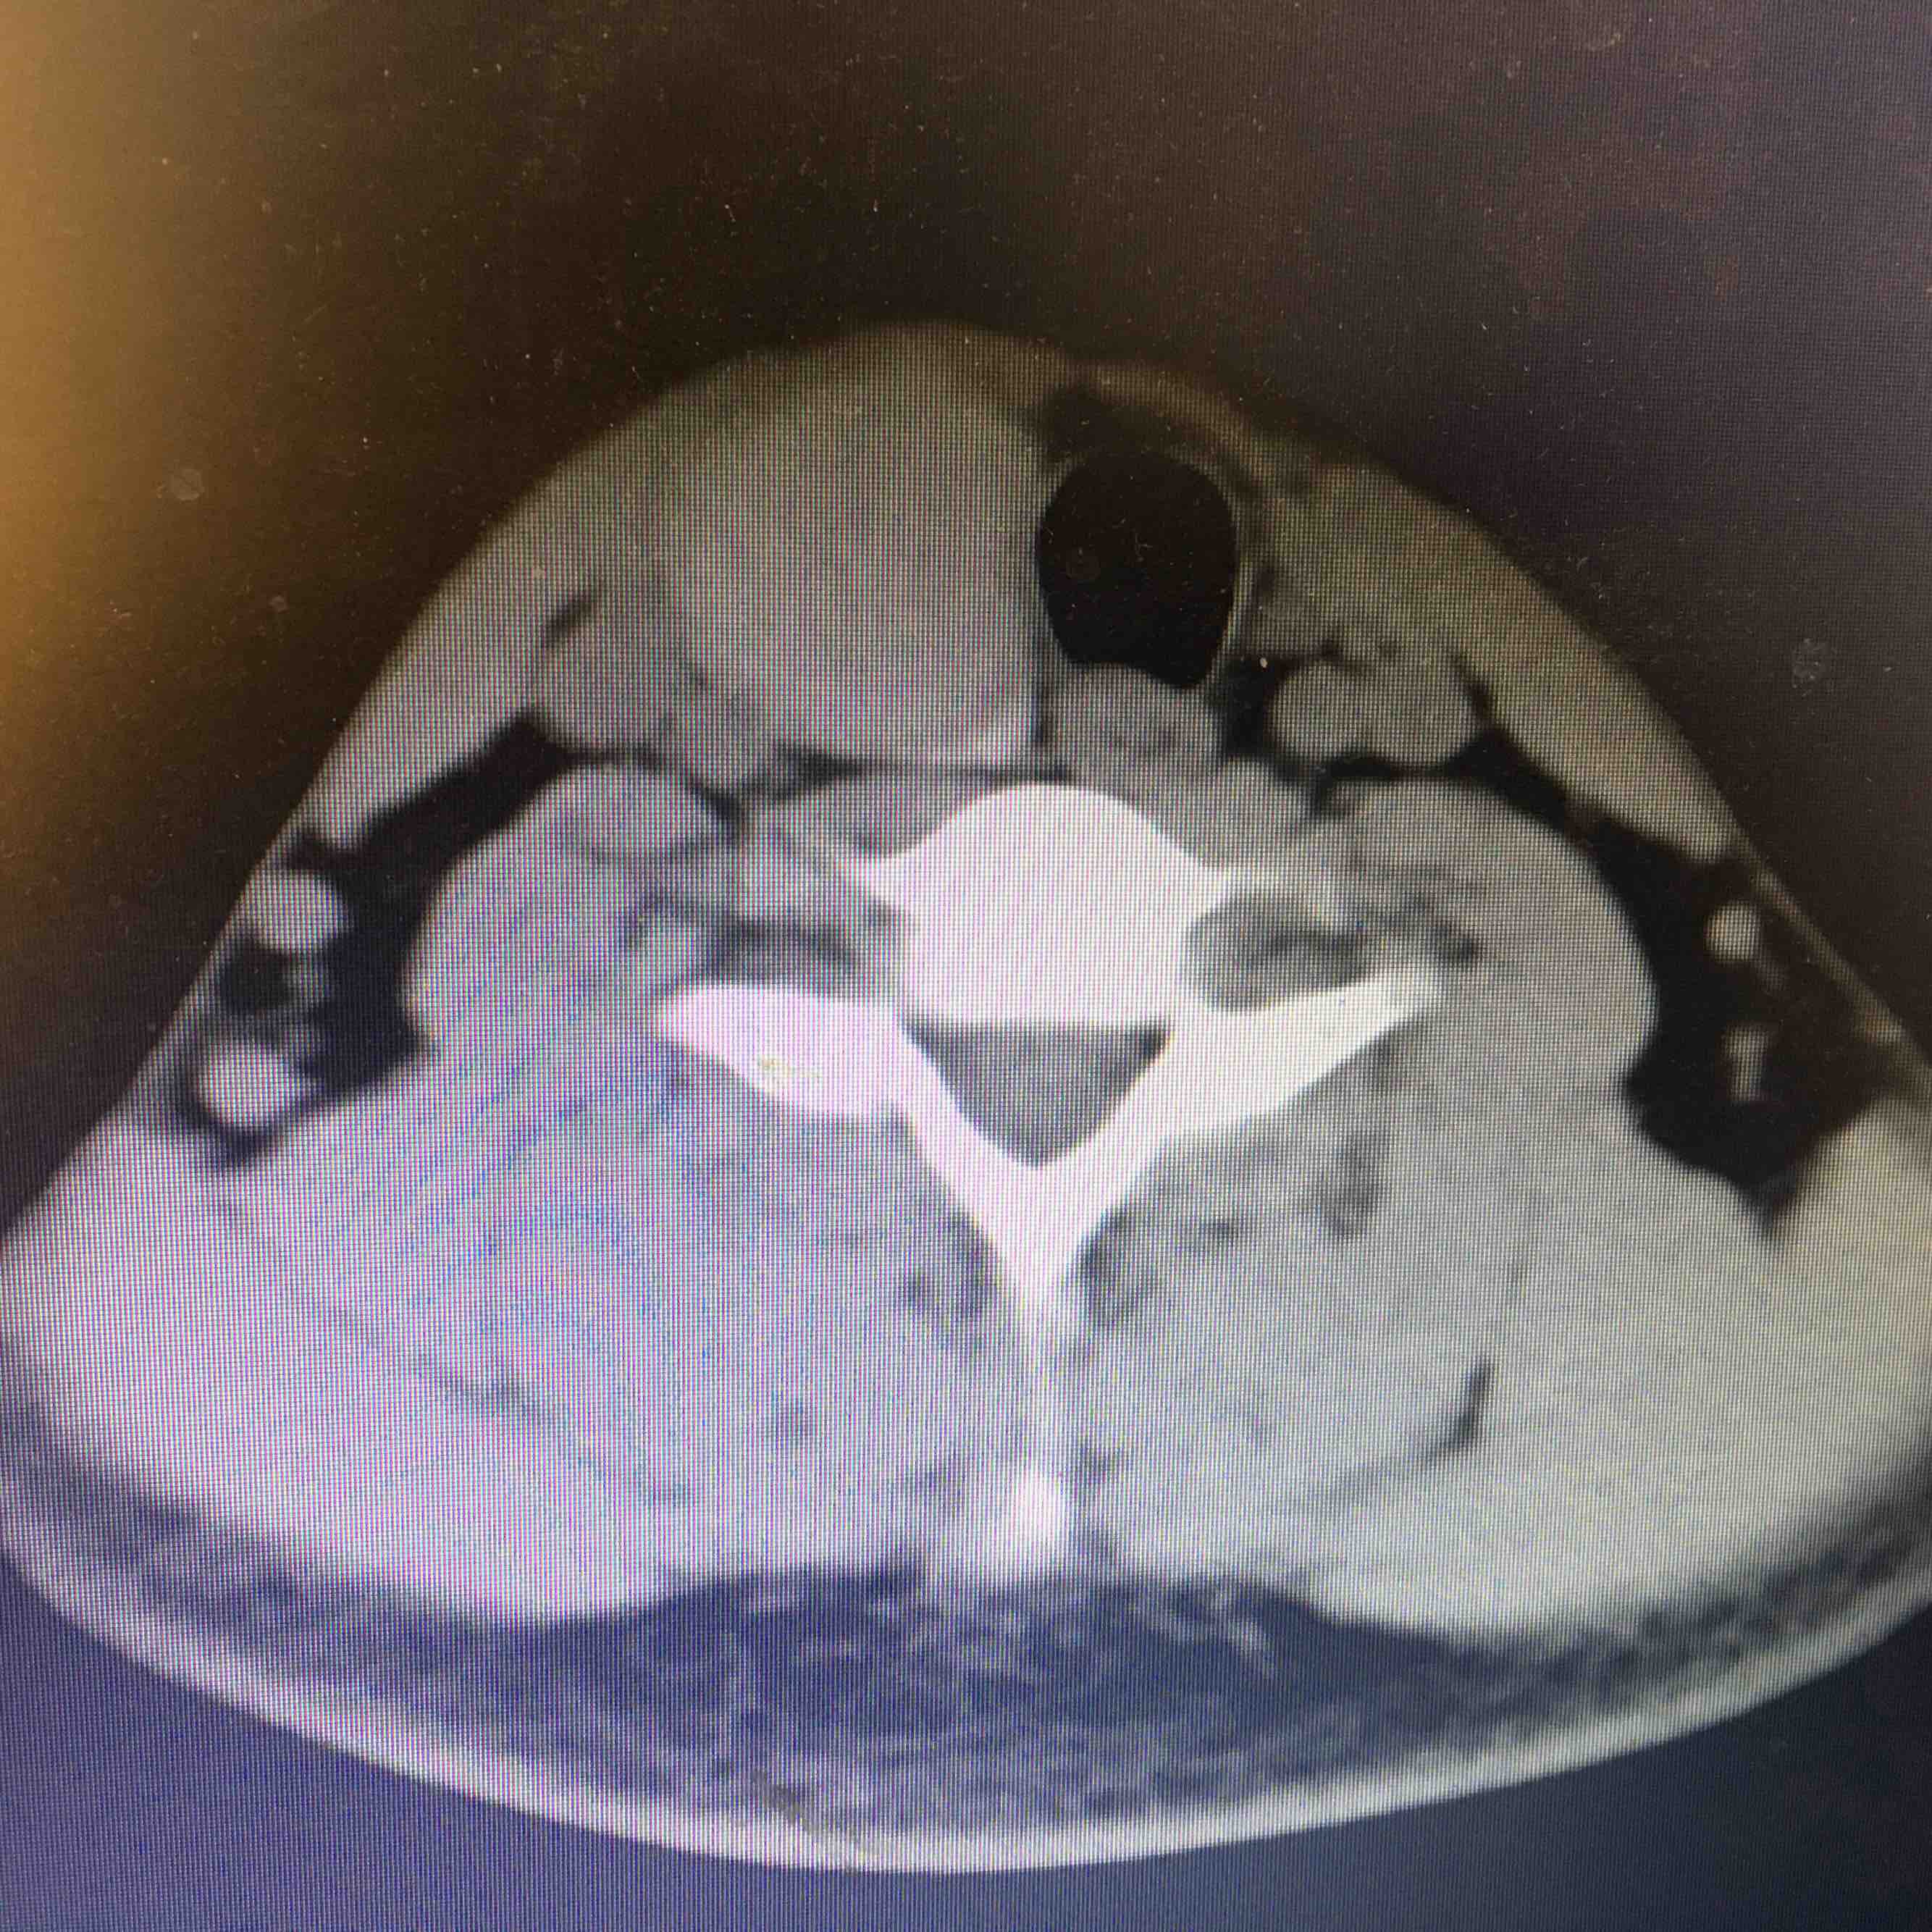

查体  颈软,气管向左侧移位,甲状腺右侧叶可触及一大小约3cm✖️3cm肿物,质韧,表面光滑,边界清晰,可随吞咽上下移动,局部压痛阴性。辅助检查  甲免五项正常。甲状腺彩超示甲状腺右侧叶囊实性病变,甲状腺左侧叶显示不出,考虑缩小。颈部CT示右侧甲状腺占位置病变,建议进一步检查,左侧及峡部甲状腺缺如,请结合临床。

诊断 甲状腺右侧叶肿物 性质待查      甲状腺左侧叶峡部缺如处理 患者要求赴上级医院进一步检查和治疗

先天性甲状腺一侧叶缺如非常少见,需要进一步完善相关检查,了解有无异位甲状腺组织。